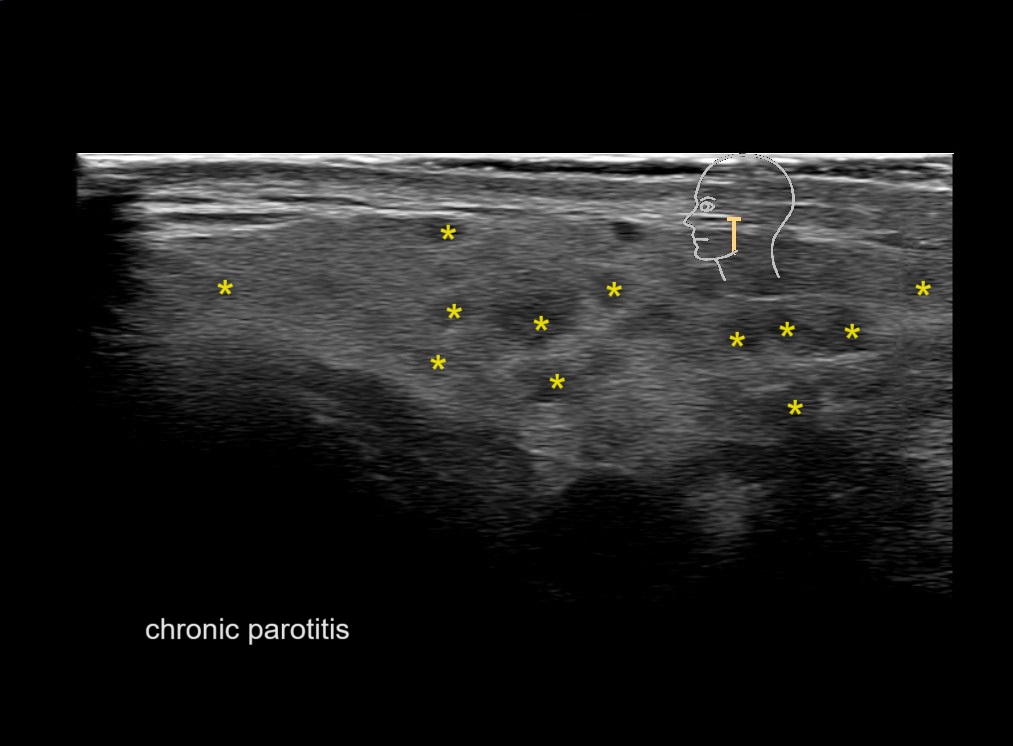

With ultrasound signs of inflammation can be visualized. Edema can be seen as a hyperechoic appearance of the subcutaneous fat, sometimes separated by hypoechoic fluid filled area’s, known as cobblestone appearance. Increased vascularization (hypervascularity) can be seen on colour Doppler. An abscess will appear as a fluid collection appearing as an irregular hypoechoic area with heterogeneous internal echoes and a thickened wall. Posterior acoustic enhancement can be present, and there is vascularity around but not within the mass. Under ultrasound guidance, abscesses can be managed by needle aspirations (18G) under antibiotic cover.

Study the first image to recognize the different layers. If you are sure about the layers, swipe to the second image to view the answer (if applicable).